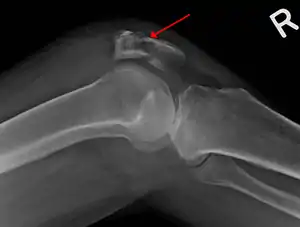

| A fracture of the patella seen on a lateral view | |

Diagnosis

Diagnosis is based on symptoms and confirmed with X-rays.[3] In children an MRI may be required.[3]